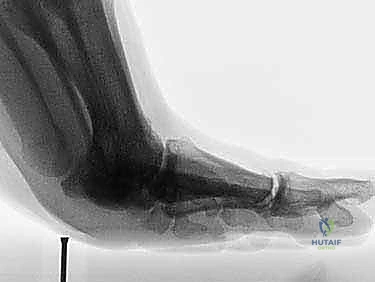

2. التصوير بالأشعة السينية (X-Rays)

يتم إجراء صور أشعة سينية بوضعيات تحمل الوزن (Weight-bearing) وبوضعيات الإجهاد (Stress views). تساعد الأشعة السينية في:

* استبعاد وجود كسور في عظام المشط أو السلاميات.

* تقييم العظام السمسمانية (البحث عن كسور أو هجرة غير طبيعية للعظام السمسمانية، مما يدل على تمزق الصفيحة).

* تقييم تضيق المسافة المفصلية.